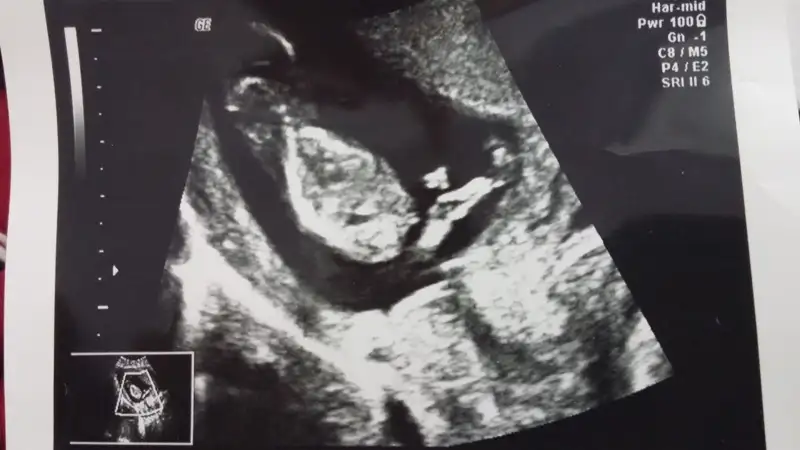

Diğer ultrason görüntülerini atıyorum, lütfen bide bunlara bakarmısın?

Eki Görüntüle 1277161 Eki Görüntüle 1277162

Canim yukari dogru bakan biaey var ama tam olarak nub mu gobek bagimi cozemedim bacaklariyla kapamis gibj:)Eki Görüntüle 1279243 Eki Görüntüle 1279245 Arkadaslar burda 12+5 gunluguz cok merak ediyorum tahmin de bulunabilirmisiz